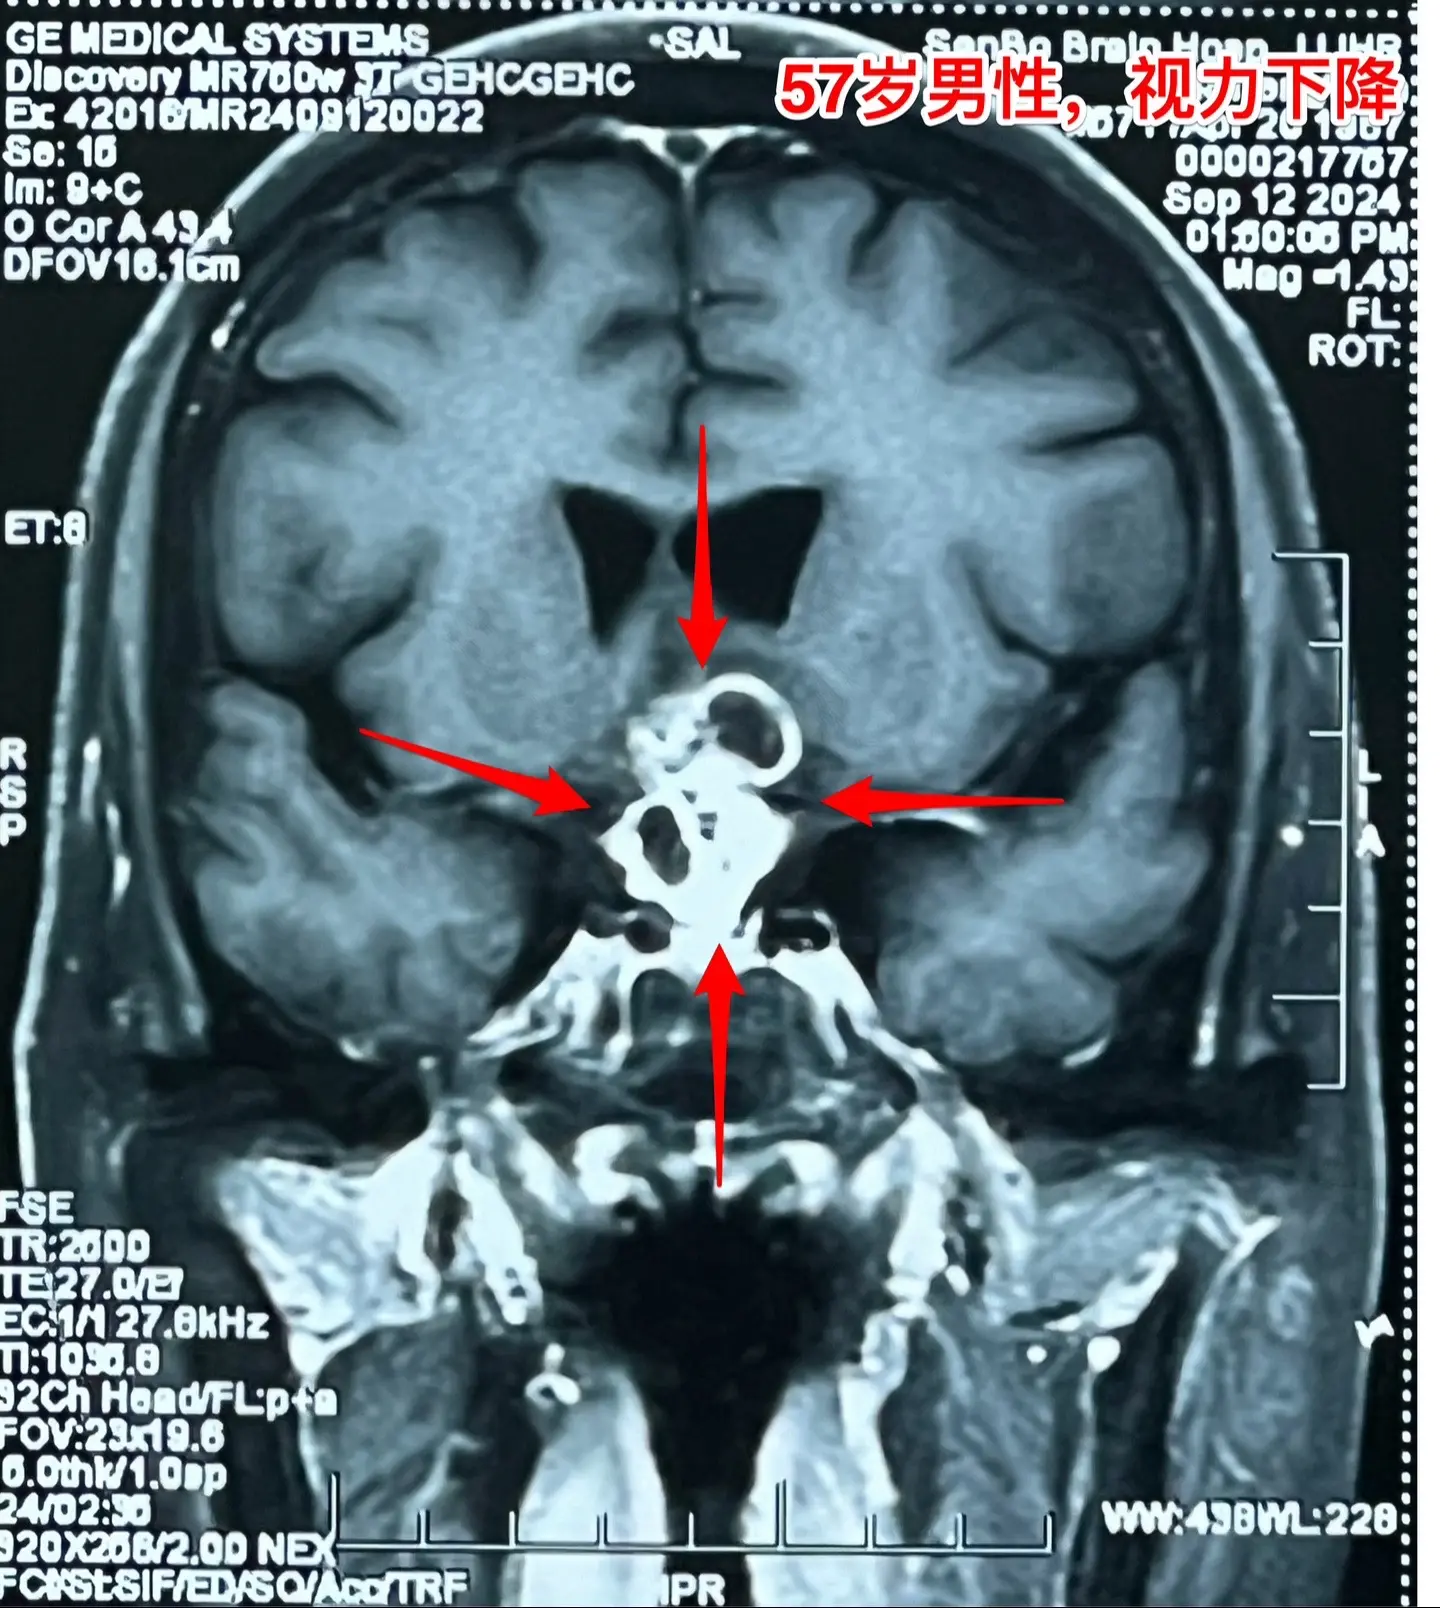

57岁男性,颅咽管瘤导致视力下降。病人因视力下降、消瘦到外院检查发现颅咽管瘤。如图所示,肿瘤体积比较大,有大量的钙化斑,是典型的造釉性颅咽管瘤。2024.9.20在我院行开颅手术,将颅咽管瘤完全切除。手术后患者视力明显改善了。十一前已经出院了,出院前体重有增长。